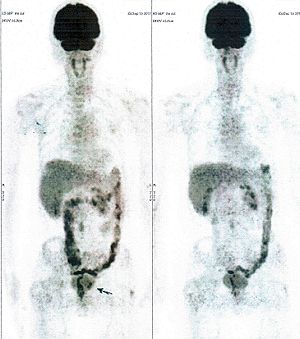

CASE NO: 3 (PROSTATE CANCER)

A middle-aged man with castration resistant prostate cancer, having failed all currently available cancer treatment, was very weak, and getting worse every day. The PET/CT scan showed he had massive bone metastases. After a few treatment, all the bone metastases went into remission. About 6 months later, he is still in remission.